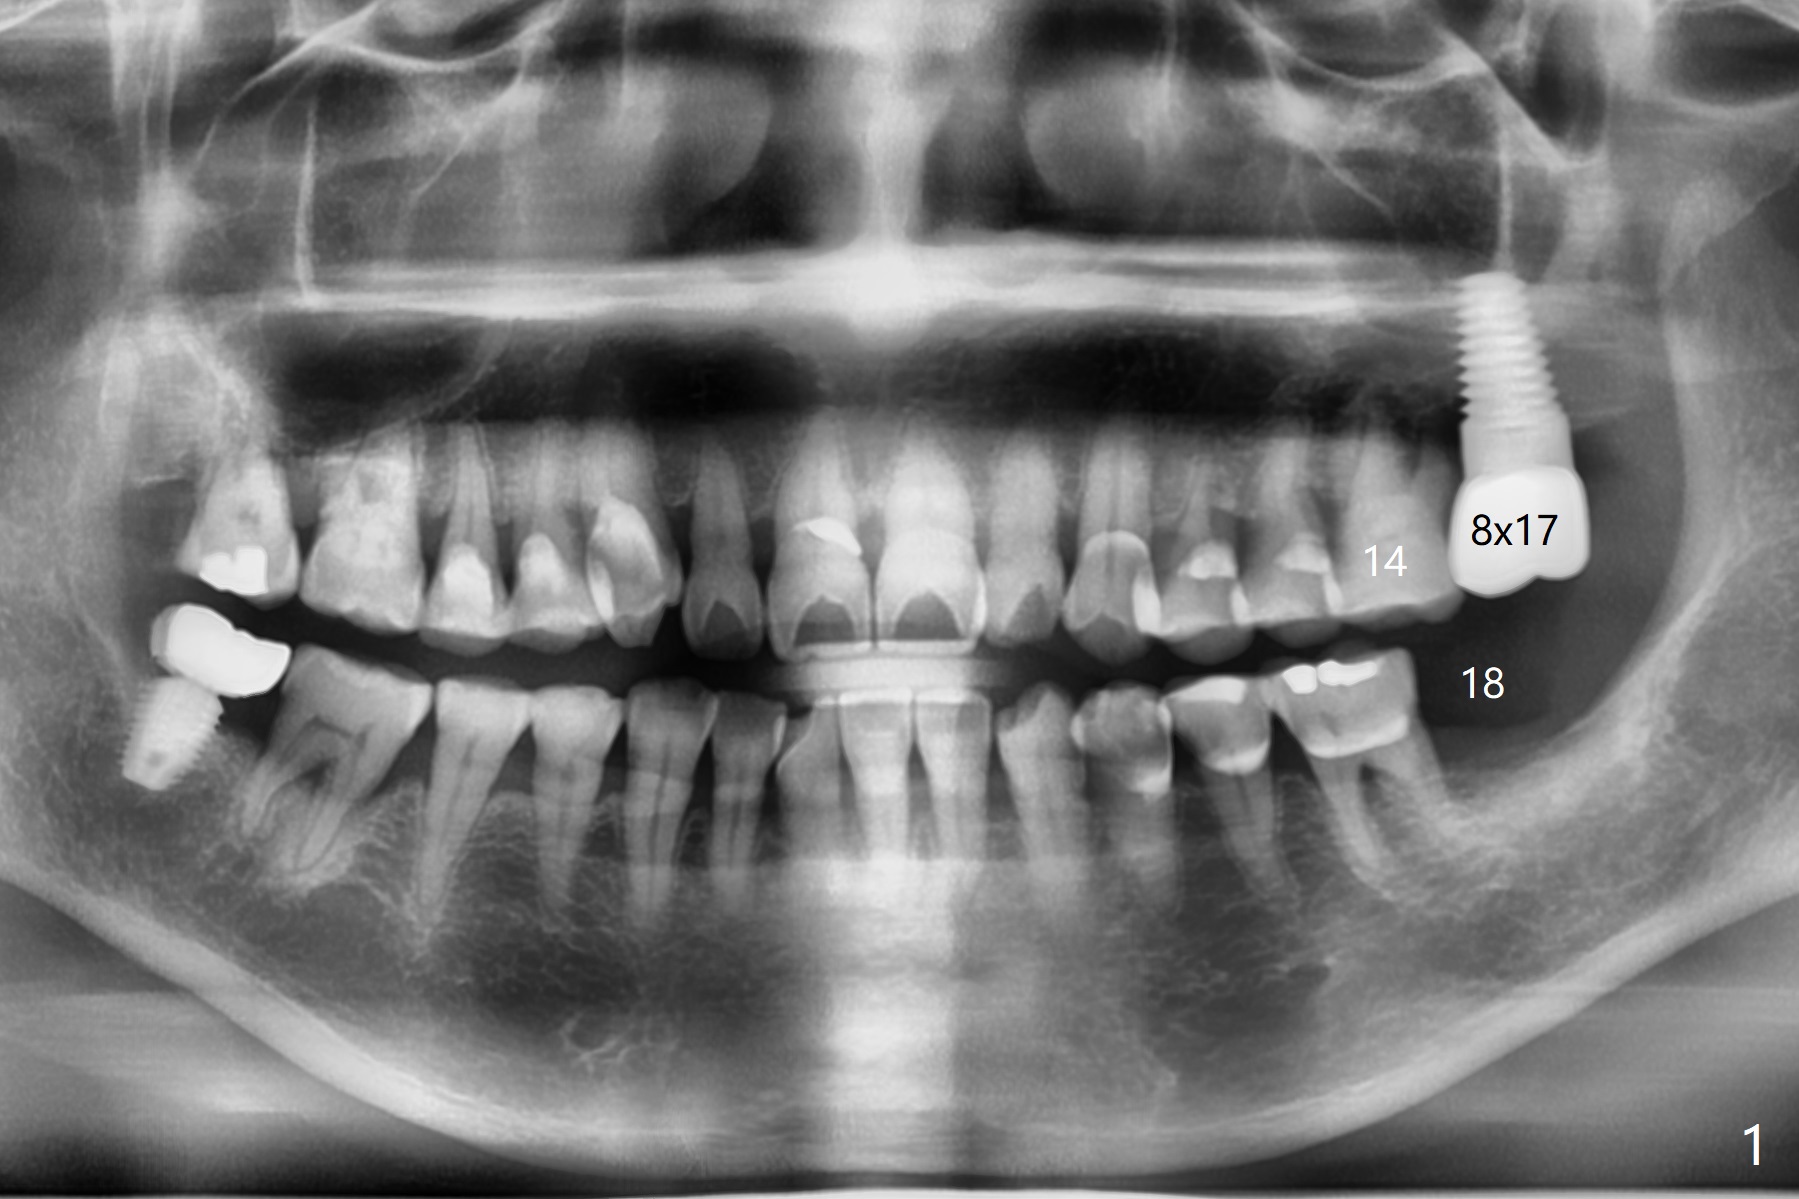

A 61-year-old woman requests implant at #14 because of mobility after exfolia-tion of the tooth #18 (Fig.1). Because of severe bone loss, especially palatal (Fig.2,3 P), osteotomy will be initiated with guide as buccal as possible (Fig.4). To reduce abutment screw loosening, a 5x11 mm tissue-level implant will be placed (Fig.5 blue (pink: abut-ment)).